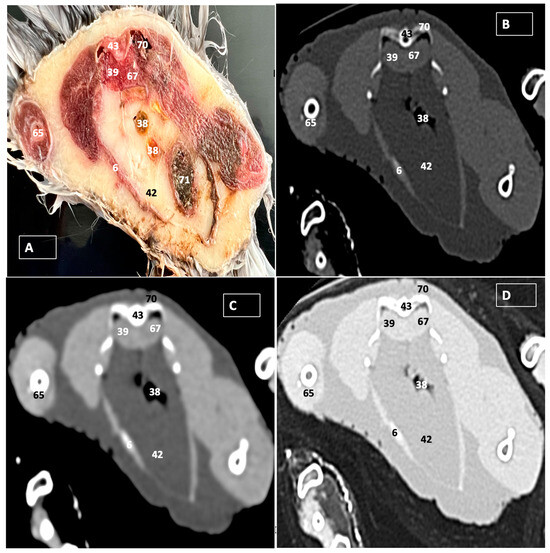

3. Results

3.1. Anatomical Dissections and Cross-Sections

3.2. Computed Tomography Images